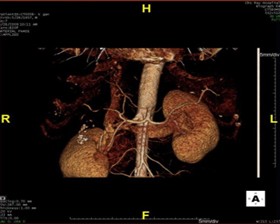

Những năm vừa qua được sự quan tâm của thủ trưởng các cấp cùng với sự đầu tư của Đảng ủy, Ban giám đốc Bệnh viện trong chẩn đoán và điều trị, bệnh viện đã trang bị nhiều máy móc hiện đại, trong đó đặc biệt có máy CT Scanner 16 Slice SIEMENS của Cộng Hòa Liên Bang Đức, cùng với sự chuyển giao kỹ thuật, công nghệ mới, các bác sỹ và kỹ thuật viên đã làm chủ hoàn toàn các kỹ thuật phức tạp mà chỉ có tuyến tỉnh và trung ương mới đáp ứng được như: Chụp CTscanner có thuốc cản quang gan ba thì, ổ bụng, lồng ngực, sọ não, hệ mạch máu bụng, chậu, chi…Trong thu dung cấp cứu, máy CT Scanner càng phát huy thế mạnh trong chẩn đoán chấn thương sọ não, chấn thương bụng kín…